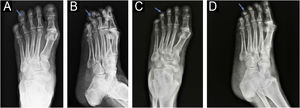

On the radiograph, bone erosion associated with the thickening of soft tissues in the distal phalanx of the left fourth toe was evident (Fig. 2). An excisional biopsy without margins was performed for histological diagnosis.

Anteroposterior (A) and lateral (B) radiographs of the left foot before the surgery: increased soft tissue density and bone erosion of the distal phalanx (blue arrow), resembling a “cup” appearance (B). Anteroposterior (C) and lateral (D) radiographs of the left foot two months after the surgery: partial recovery of bone structure.